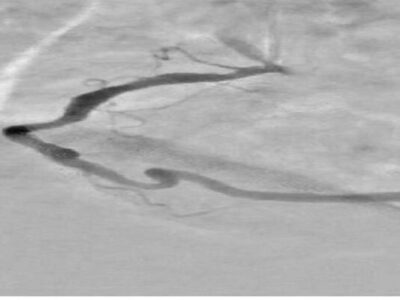

آخوندی با اشاره به دلایل انتخاب این تحقیق، توضیح داد: در آنژیوگرافی قلب، تداخل سایههای ناشی از بافتها و استخوانهای قفسه سینه و همچنین حرکات تنفسی و ضربان قلب باعث میشود تشخیص دقیق عروق کرونری دشوار شود. این مسئله منجر به نیاز به تزریق بیشتر ماده حاجب و دریافت دوز بالاتر اشعه توسط بیمار میشود.

این دانش آموخته دانشگاه صنعتی امیرکبیر با تاکید بر اینکه نتایج این تحقیق موجب بهبود وضوح تصاویر و افزایش دقت در نمایش عروق کرونری قلب شده است، اظهار کرد: این تحقیق به طور ویژه در جهت ارتقای فناوری پردازش تصویر پزشکی و بومیسازی روشهای نوین شبکههای عصبی گامی مؤثر برداشته است؛ چرا که این طرح با کاهش زمان پردازش و افزایش دقت، نسبت به سایر الگوریتمهای سنتی امکان بهرهبرادری بهتر در حوزههای کاربردی را فراهم میسازد.

وی بخش نوآورانه طرح را شامل استفاده از شبکه خودرمزگذار هدایتشده برای بازسازی پسزمینه تصاویر حاوی ماده حاجب از تصاویر بدون ماده حاجب ذکر کرد و افزود: همچنین در طراحی شبکههای عصبی عمیق متناسب بودن با تصاویر آنژیوگرافی بهعلت مقیاس خاکستری آنها و ظرافت عروق در طراحی لحاظ شدهاست.

آخوندی ویژگیهای این طرح را شامل افزایش وضوح عروق کرونری در تصاویر آنژیوگرافی، کاهش نیاز به تزریق مقدار زیاد ماده حاجب و در نتیجه کاهش خطرات مرتبط با آن برای بیمار دانست و افزود: همچنین نسبت به روشهای سنتی، زمان پردازش تصاویر را به طور قابل توجهی کاهش میدهد و میتواند حتی با در اختیار داشتن یک تصویر تکی حاوی ماده حاجب نیز عمل اصلاح و پردازش را انجام دهد. در نهایت، بهرهگیری از فناوری شبکههای عصبی عمیق، امکان استخراج و بازسازی هوشمند پسزمینه و جداسازی بهتر عروق را فراهم میکند و طرح را از نظر علمی و کاربردی در سطح روشهای نوین پردازش تصویر پزشکی قرار میدهد.